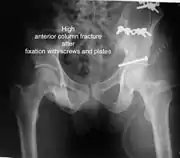

High anterior column fracture 3 D CT scan picture

High anterior column fracture after fixation with screws and plates